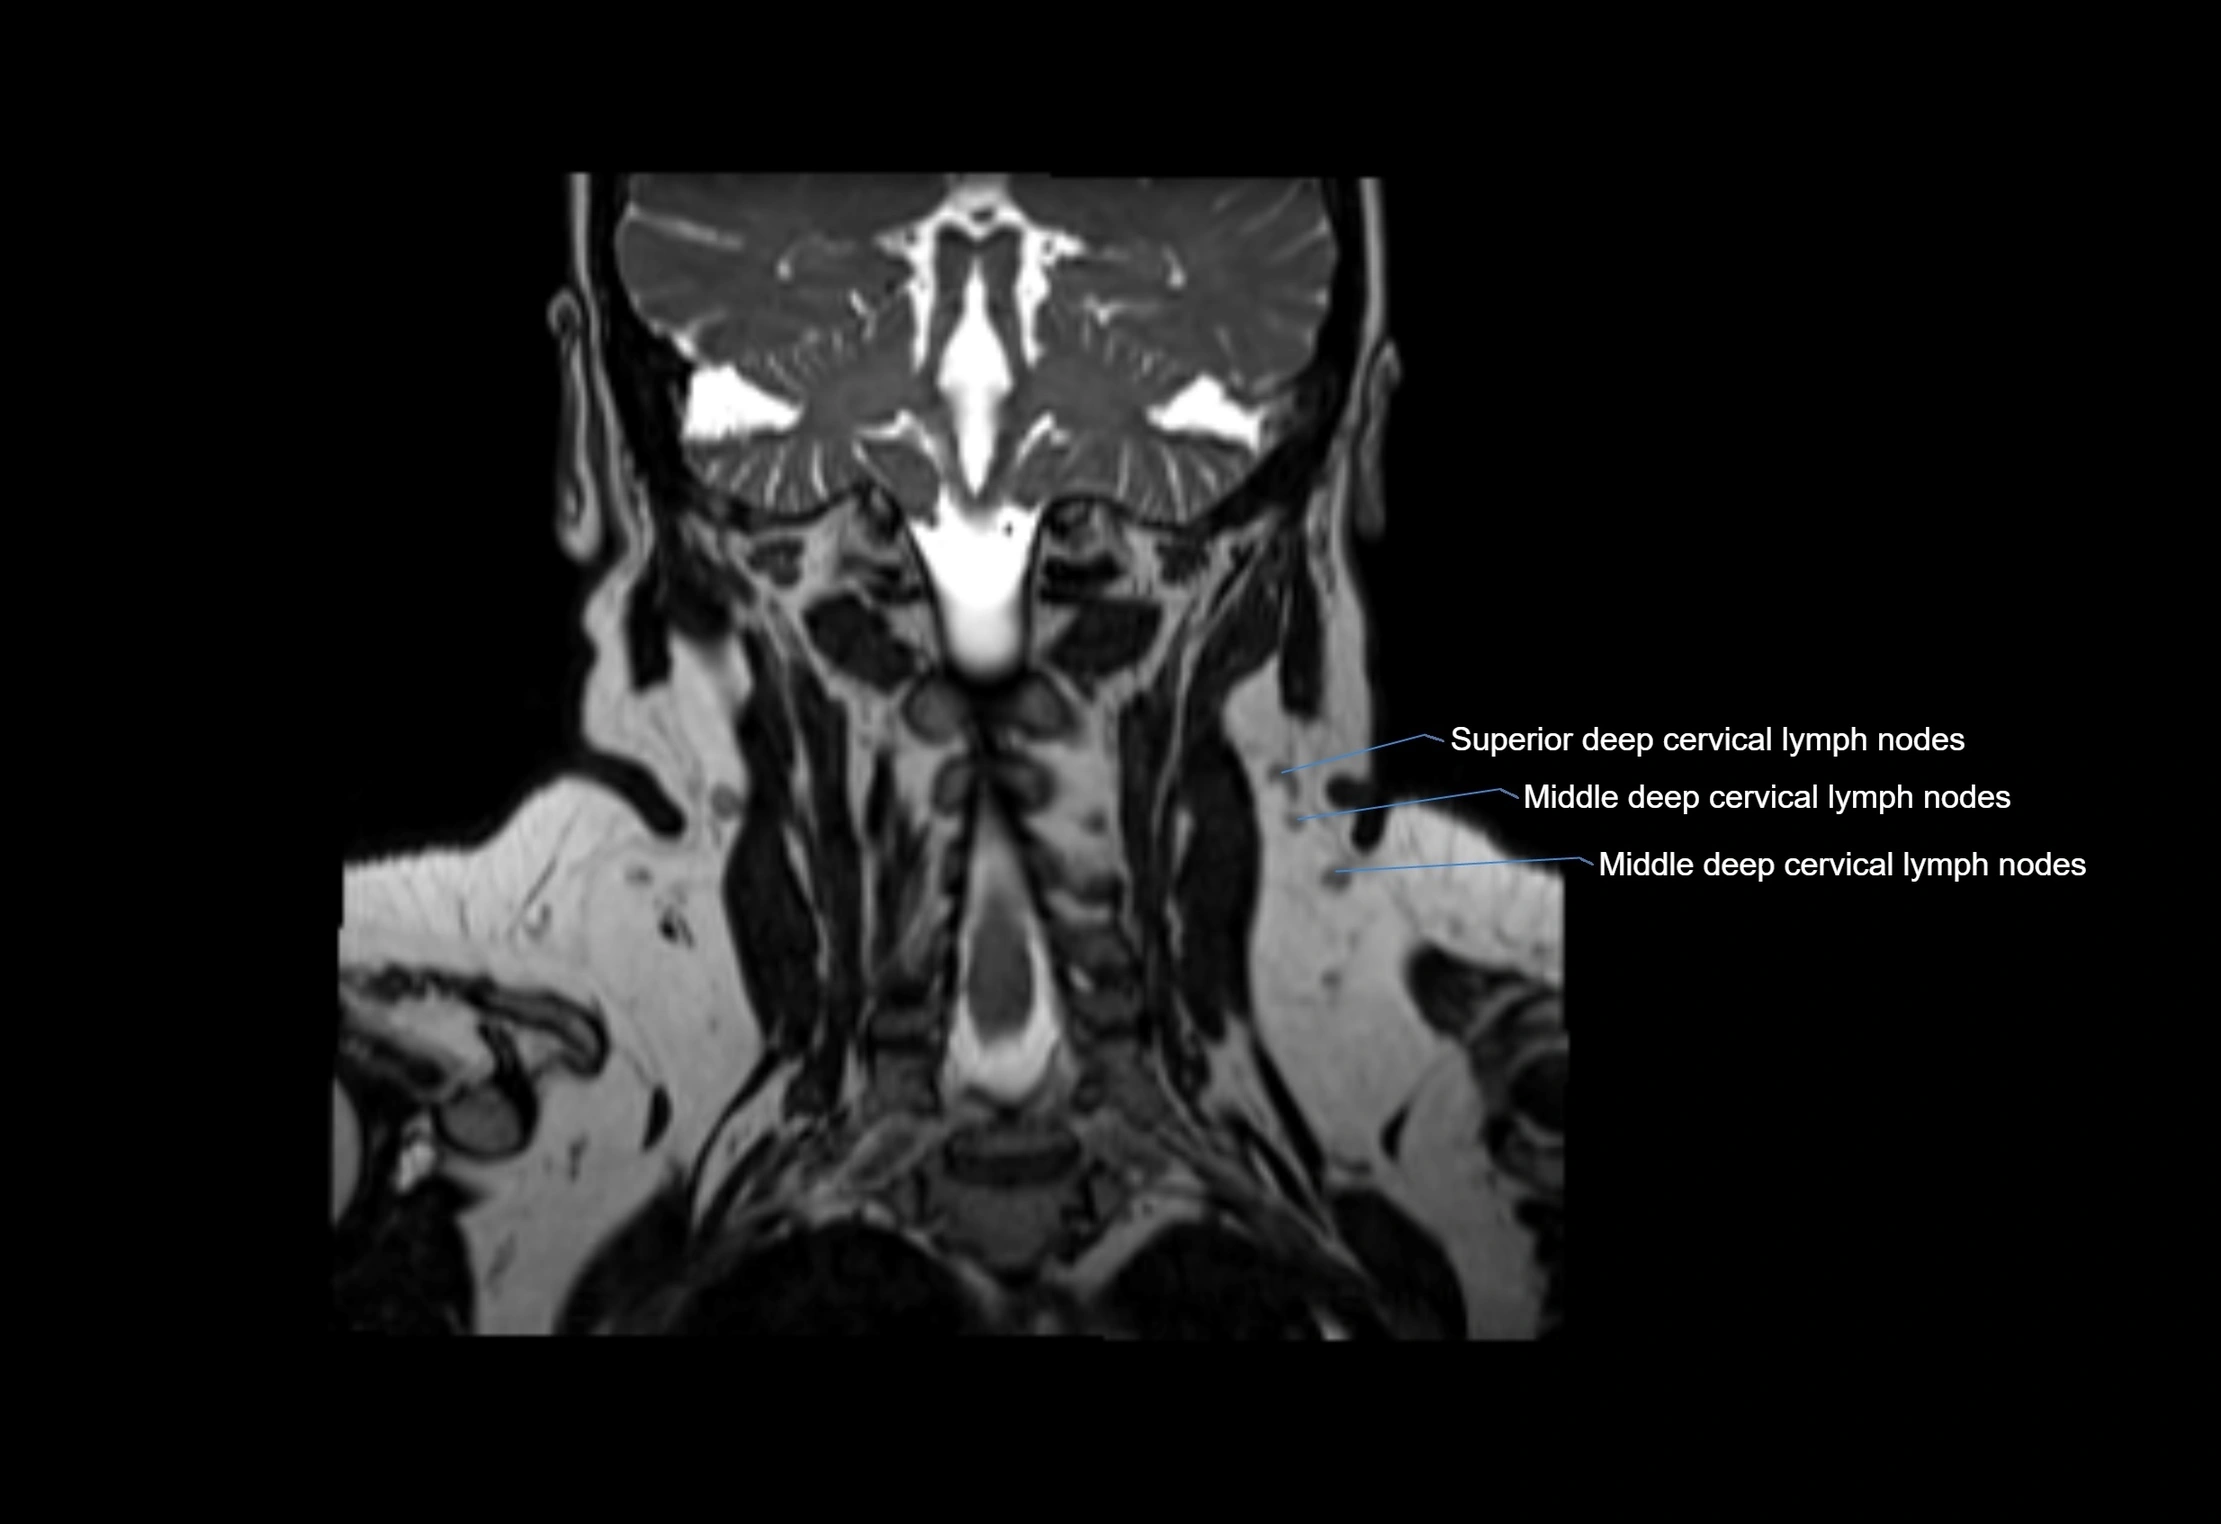

Location

• Found along primary lymph node chains, including preauricular, submandibular, parotid, and occipital regions

• Embedded in subcutaneous fat or superficial fascia, often lateral or posterior to primary nodes

• Variable in number; may occur unilaterally or bilaterally, depending on individual anatomy

MRI Appearance

T2-weighted images:

• Nodes show intermediate signal, with surrounding fat bright

• Useful for detecting edema, inflammation, or infiltration